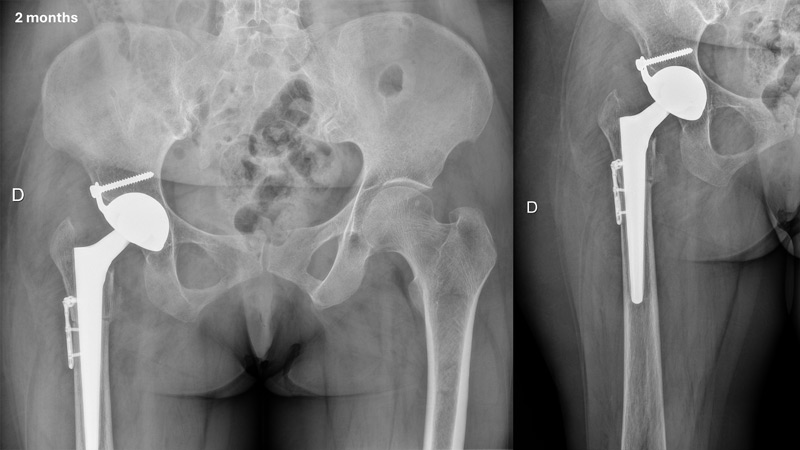

Pre-operative X-rays and CT-scan

Management of a hip dysplasia in a middle-aged woman:  Pre-operative X-rays and CT-scan